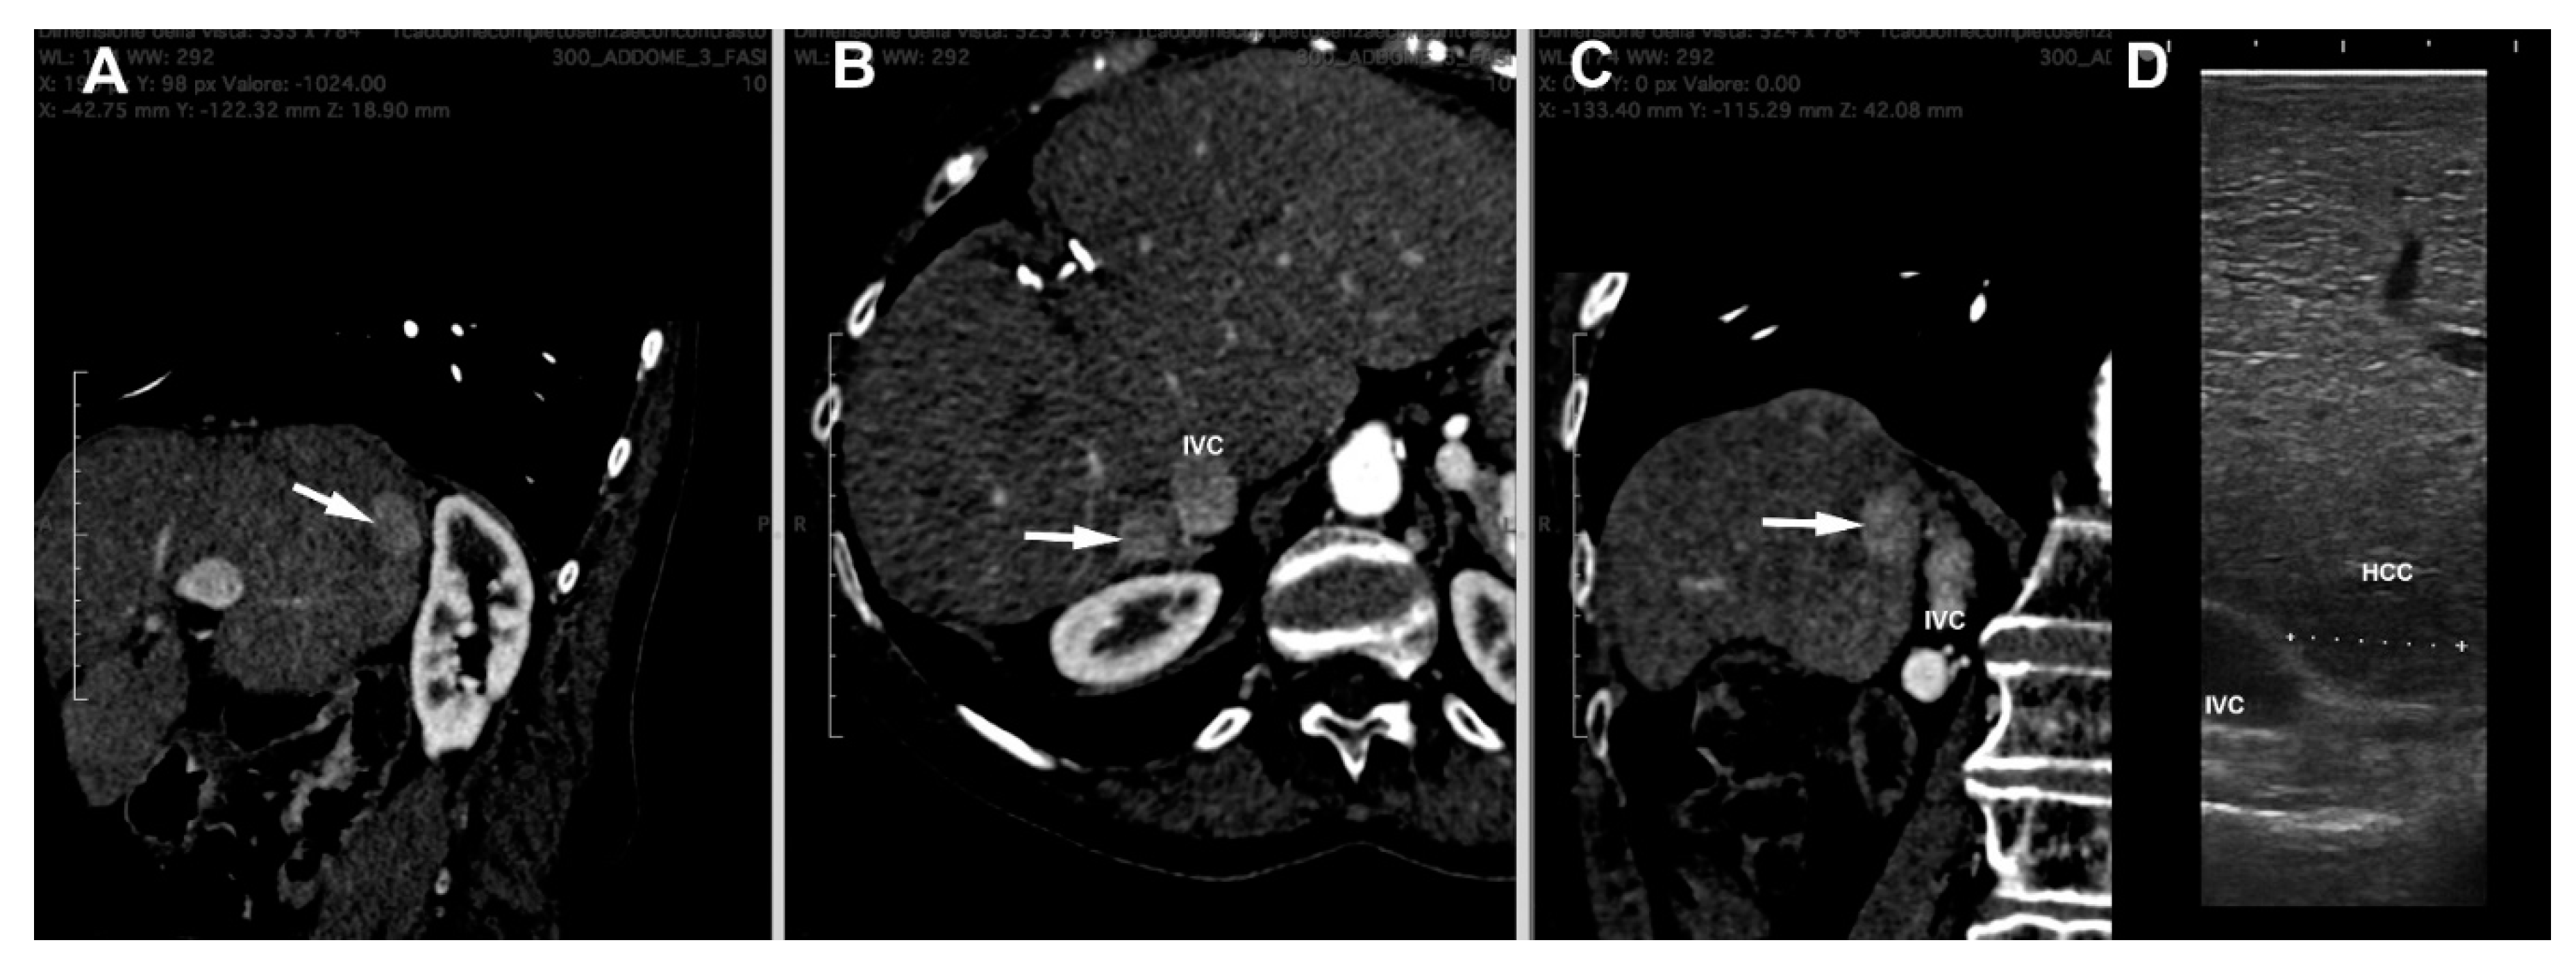

4. LUS Evaluation

- Santambrogio, R.; Cigala, C.; Barabino MMaggioni, M.; Scifo, G.; Bruno, S.; Bertolini, E.; Opocher, E.; Bulfamante, G. Intraoperative ultrasound for prediction of hepatocellular carcinoma biological behavior: Prospective comparison with pathology. Liver Int. 2018, 38, 312–320. [Google Scholar] [CrossRef]

- Santambrogio, R.; Barabino, M.; D’Alessandro, V.; Iacob, G.; Opocher, E.; Gemma, M.; Zappa, M.A. Micronvasive behaviour of single small hepatocellular carcinoma: Which treatment? Updates Surg. 2021, 73, 1359–1369. [Google Scholar] [CrossRef]